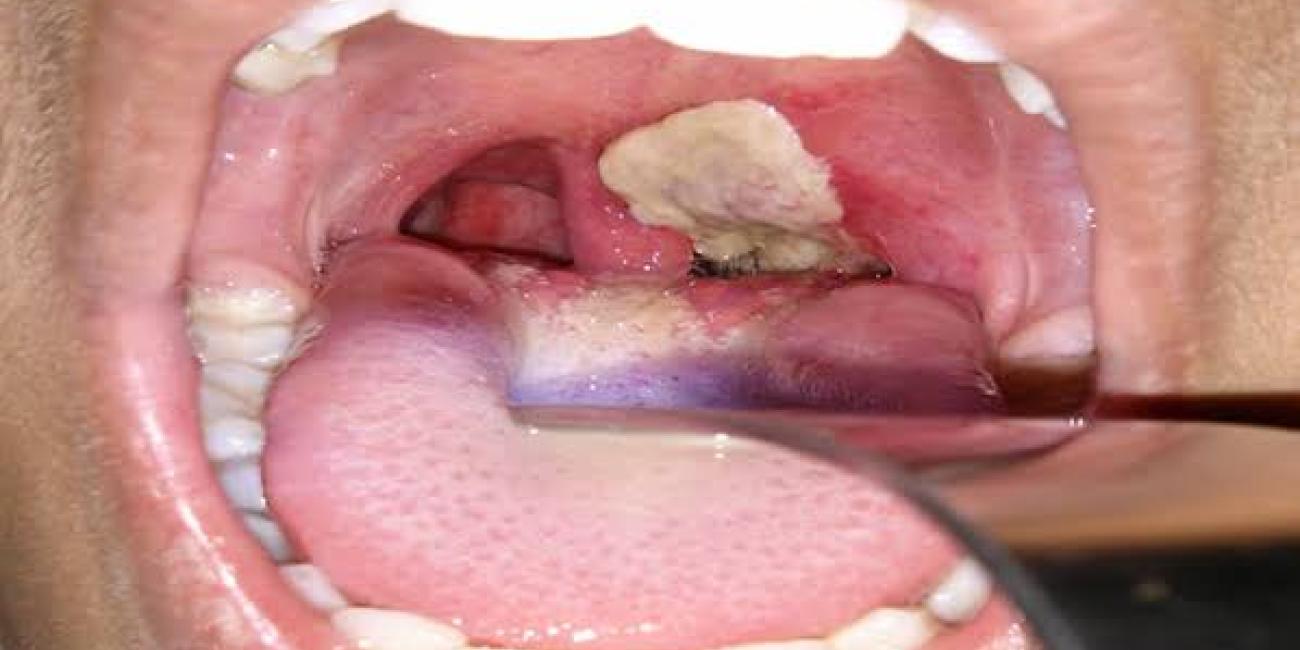

Diphtheria, a highly infectious disease caused by Corynebacterium diphtheriae, typically targets the nose and throat, but in some cases, it can affect the skin. It spreads rapidly through respiratory droplets, contaminated surfaces, or direct contact with an infected individual. The disease is particularly fatal in unvaccinated children, often leading to severe respiratory complications and heart failure if untreated.